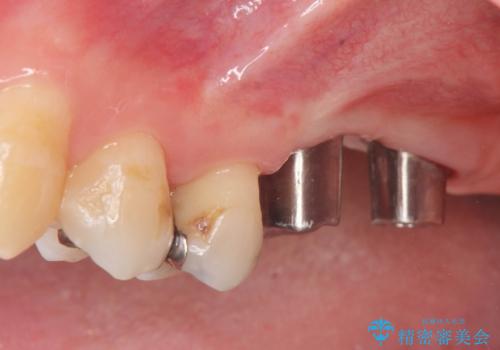

上顎奥歯のインプラント治療

- 奥歯を失い咬合機能の回復のためインプラント治療を希望され来院されました。

奥歯を2本失うと、他の歯の負担が増加し残っている歯の状態が悪くなるリスクがあります。

しっかりと咬合機能の回復できるインプラント治療を計画します。

- 88万円(インプラント×2・チタンカスタムアバットメント×2・ジルコニアクラウン×2・仮歯×2)費用は治療当時の料金となります